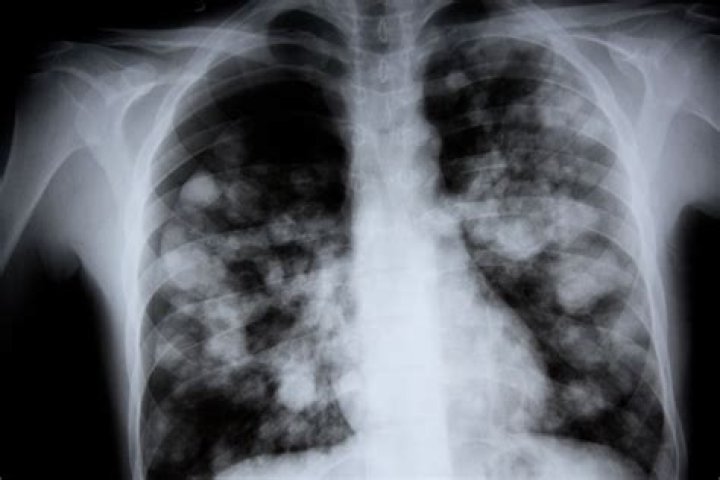

The obituary of Chad Allan, a resident of Winnipeg, Manitoba, Canada, who passed away due to white lung pneumonia, has been published. White lung pneumonia is a severe lung infection caused by the bacteria Streptococcus pneumoniae. It is characterized by the accumulation of fluid and white blood cells in the lungs, giving them a white appearance. This condition can be fatal if not treated promptly with antibiotics.

• White lung pneumonia: A severe form of pneumonia characterized by the accumulation of fluid and white blood cells in the lungs.

White lung pneumonia: A severe form of pneumonia characterized by the accumulation of fluid and white blood cells in the lungs.

White lung pneumonia is a severe form of pneumonia that is characterized by the accumulation of fluid and white blood cells in the lungs. This condition can be fatal if not treated promptly with antibiotics. In the case of Chad Allan, his obituary states that he passed away due to white lung pneumonia. This indicates that white lung pneumonia was the cause of his death.